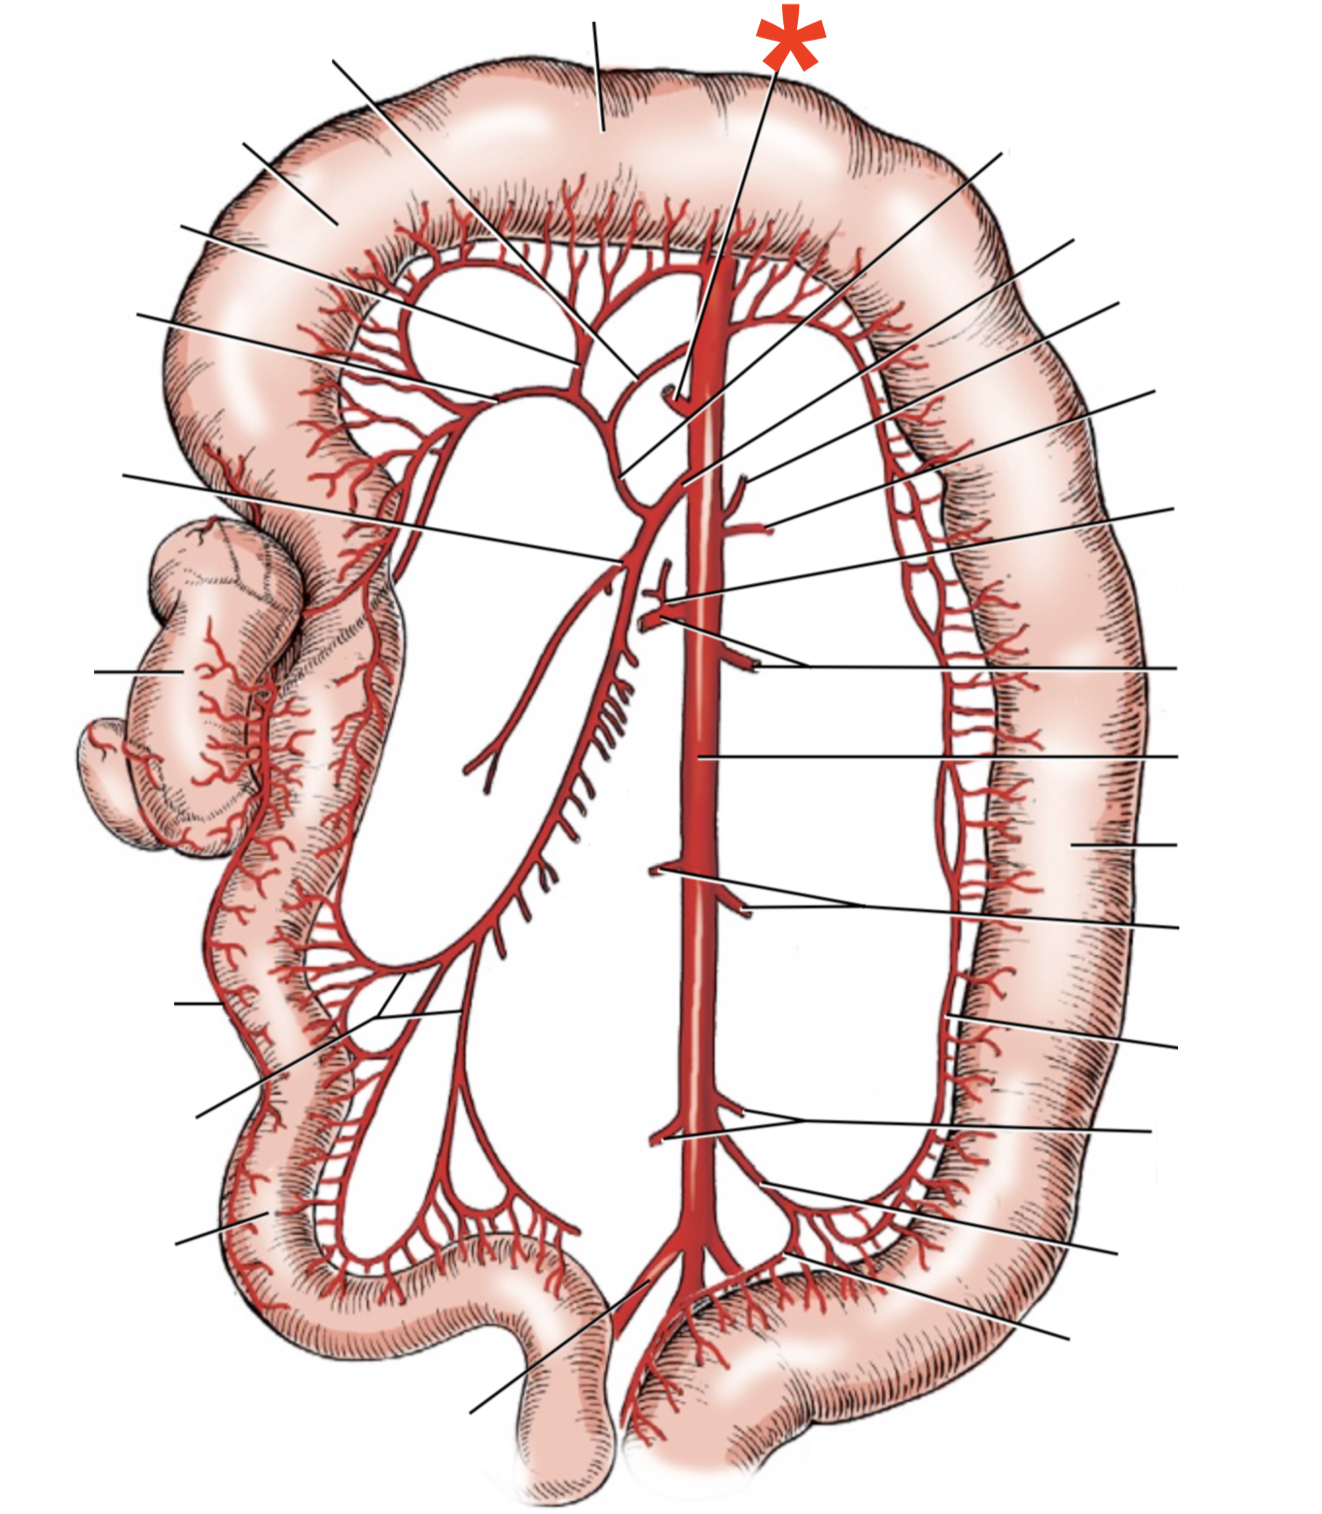

13

A

A. mesenterica cranialis

14

A

A. mesenterica caudalis

15

A

A. pancreaticoduodenalis caudalis

16

A

Aa. jejunales

17

A

A. ilei

- Anastomises with r. ileus mesenterialis a. iliocolica

18

A

A. ileocolica

19

A

A. colica dextra

20

A

A. colica media

21

A

A. mesenterica caudalis

22

A

A. colica sinistra

23

A

A. rectalis cranialis

24

A

A. ileocolica

25

**A.** **caecalis**

**R.** **ilei** **mesenterialis**

List the branching of *a.* *mesenterica* *caudalis*

* *A. colica sinistra*

* *A. rectalis cranialis*

List the branches of *a.* *mesenterica* *cranialis*

* *A.* *pancreaticoduodenalis* *caudalis*

* *Aa. jejunalis*

* *A. ilei*

* Common trunk

* A. colica media

* A. colica dextra

* *A. ileocolica*

* *R. ilei mesenterialis*

* *A. cecalis*

* *R. colicus*